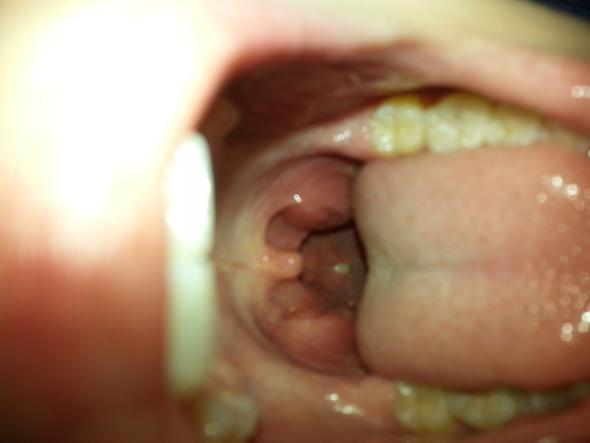

Weißer punkt auf mandel ohne halsschmerzen. Ich hatte letzten Monat einen kleinen weißen Punkt auf meiner rechten Mandel entdeckt. Weiße Beläge auf den Mandeln entstehen durch Ablagerung von Speiseresten Schleim Zellabfällen oder Eiter in den Furchen der Gaumenmandeln. Die Mundgeruch hervorrufen können.

Mandelsteine Tonsillensteine sind weiß-gelbliche Gebilde die aus verschiedenen Substanzen in den Gaumenmandeln entstehen. Wieder andere berichten von Steinen in den Mandeln die manchmal herauskämen und dann einen schlechten Geschmack im Mund verursachen. Mit dem Begriff Halsschmerzen ist eine bakterielle Halsinfektion gemeint die zur Bildung von weißen Flecken auf den Mandeln führen kann.

Sie sind wenige Millimeter groß von meist fester oder krümeliger Konsistenz und können Mundgeruch verursachen. Weil er von Bakterien gebildet wird. Diese Antwort wurde bewertet.

Weißer Punkt auf rechter Mandel ohne Symptome Schmerzen. Jedoch ohne jegliche Halsschmerzen. Diese Antwort wurde bewertet.

Viele die weiße Punkte auf den Mandeln haben oder ab und an weiße Stippen im Hals finden die besonders übel riechen fragen sich was diese weißen Flecken auf den Mandeln eigentlich sind. Weißer Belag auf den Mandeln ist ein Anzeigen dafür dass sich Eiter gebildet hat.